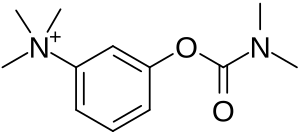

| Medication | Acetylcholinesterase inhibitors (neostigmine, pyridostigmine), immunosuppressants[1] |

Edrophonium test

Acetylcholinesterase inhibitors

Acetylcholinesterase inhibitors can provide symptomatic benefit and may not fully remove a person's weakness from MG.[47] While they might not fully remove all symptoms of MG, they still may allow a person the ability to perform normal daily activities.[47] Usually, acetylcholinesterase inhibitors are started at a low dose and increased until the desired result is achieved. If taken 30 minutes before a meal, symptoms will be mild during eating, which is helpful for those who have difficulty swallowing due to their illness. Another medication used for MG, atropine, can reduce the muscarinic side effects of acetylcholinesterase inhibitors.[48] Pyridostigmine is a relatively long-acting drug (when compared to other cholinergic agonists), with a half-life around four hours with relatively few side effects.[49] Generally, it is discontinued in those who are being mechanically ventilated as it is known to increase the amount of salivary secretions.[49] A few high-quality studies have directly compared cholinesterase inhibitors with other treatments (or placebo); their practical benefit may be such that it would be difficult to conduct studies in which they would be withheld from some people.[50]